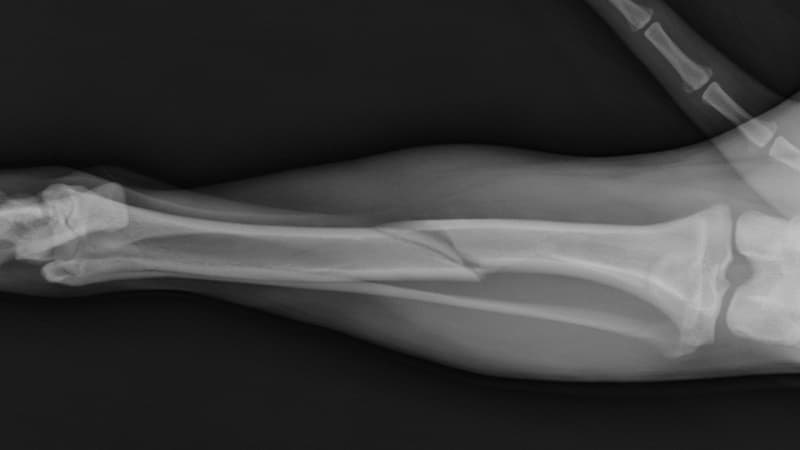

Liền xương là quá trình sinh lý tự nhiên của cơ thể giúp phục hồi phần xương bị gãy, nứt hoặc tổn thương. Trong quá trình này, các mô xương mới được hình thành để tái tạo cấu trúc và khôi phục chức năng vững chắc của xương. Mọi trường hợp gãy xương (dù do chấn thương hay can thiệp phẫu thuật) đều phải trải qua các giai đoạn của quá trình liền xương với những phản ứng sinh học đặc trưng.

Quá trình phục hồi tại vị trí gãy xương là một chuỗi phản ứng sinh học phức tạp. Về cơ bản, quá trình này được chia thành 4 giai đoạn liền xương, tuy nhiên các giai đoạn thường diễn ra chồng chéo và không tách biệt hoàn toàn.

2.1. Giai đoạn hình thành máu tụ sau gãy xương (ngày 1 – ngày 5)

Giai đoạn đầu tiên của quá trình liền xương bắt đầu ngay sau khi xương bị gãy. Lúc này các mạch máu nuôi xương và màng xương bị tổn thương sẽ vỡ ra, khiến máu tụ lại xung quanh ổ gãy. Khối máu tụ nhanh chóng đông lại và tạo thành một cấu trúc tạm thời, đóng vai trò như “giá đỡ sinh học” để chuẩn bị cho các bước phục hồi tiếp theo.